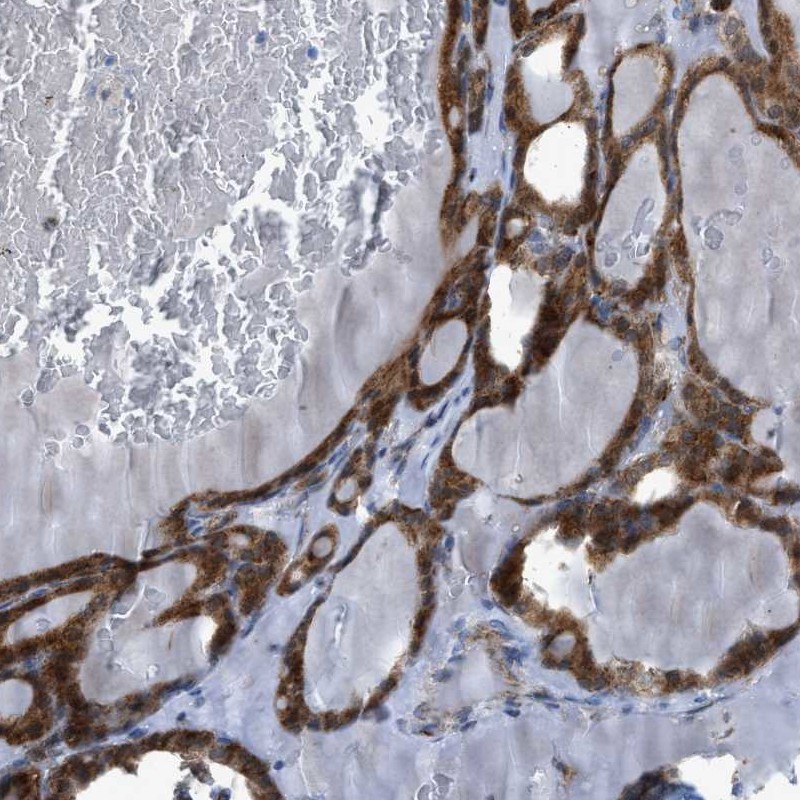

Immunohistochemical staining of human thyroid gland shows cytoplasmic positivity in glandular cells.